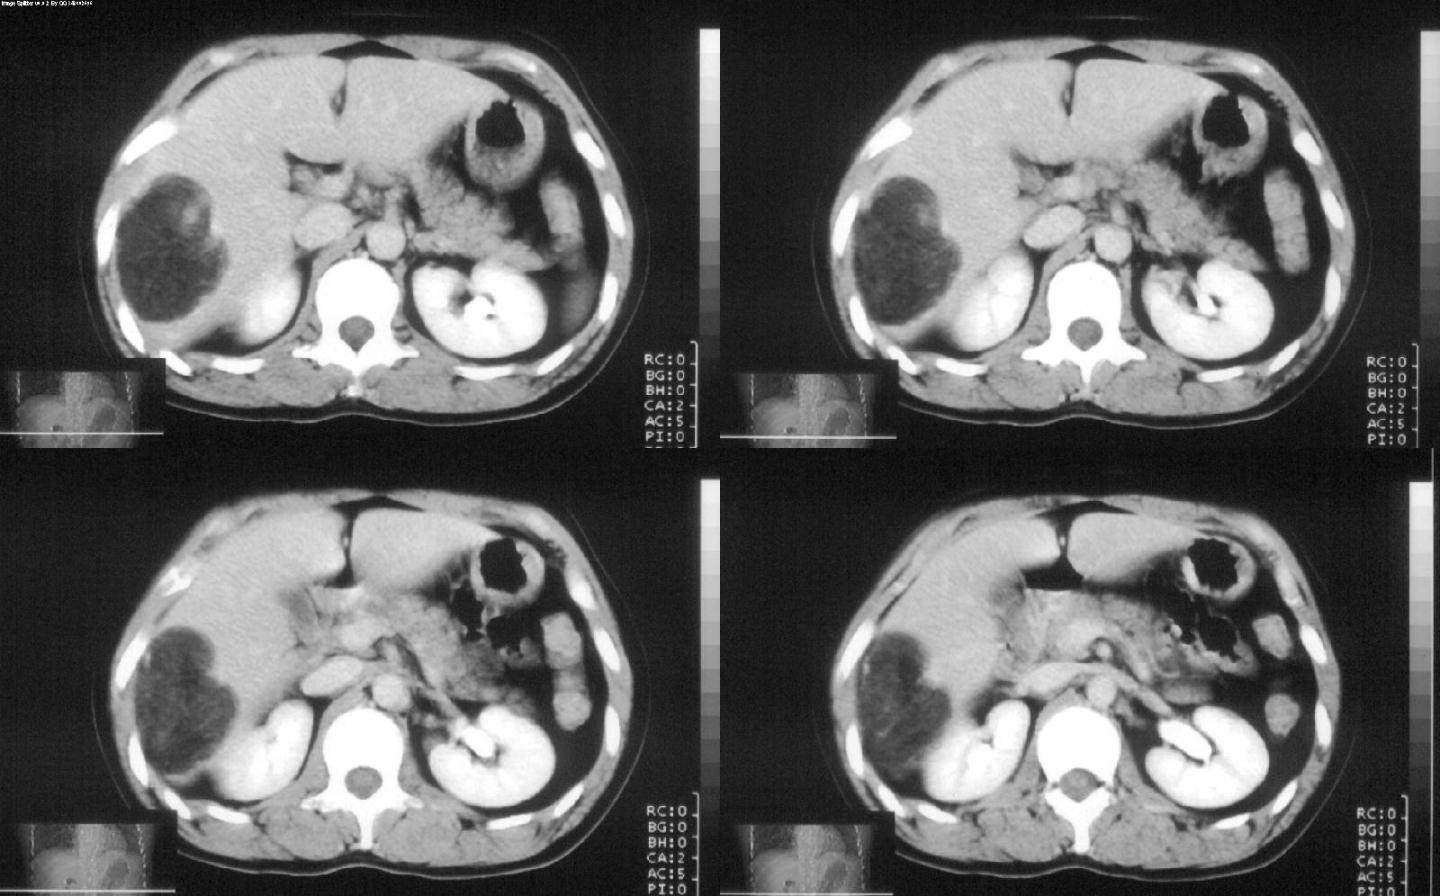

标题: CT28180:女性,42岁。体检时发占位。 [打印本页]

标题: CT28180:女性,42岁。体检时发占位。

支持 肝右叶血管平滑肌脂肪瘤。

病灶多种成分,以脂肪为主,可见强化的血管肌肉成分,边界较清晰,综合考虑血管平滑肌脂肪瘤可能性大

考虑血管平滑脂肪瘤,不能完全除外脂质丰富的肝癌

支持 肝右叶血管平滑肌脂肪瘤